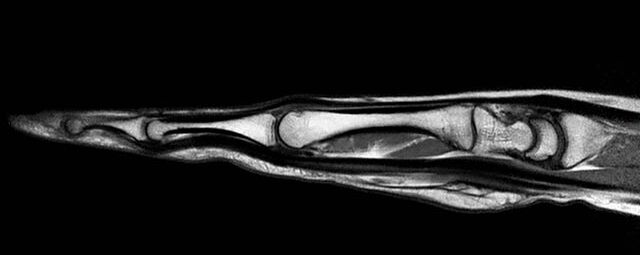

Gelenke

Hand

• Beurteilung von Knochen, Bändern und anderen Weichteilstrukturen der Gelenke nach Unfall.

• Arthrosediagnostik (Knorpelschaden)

• Impingement-Symptomatik

• Ursachenklärung bei wiederholter spontaner Gelenkluxation

• Ausbreitungsdiagnostik bei Gelenkentzündung, z.B. im Rahmen von rheumatischen Grunderkrankungen